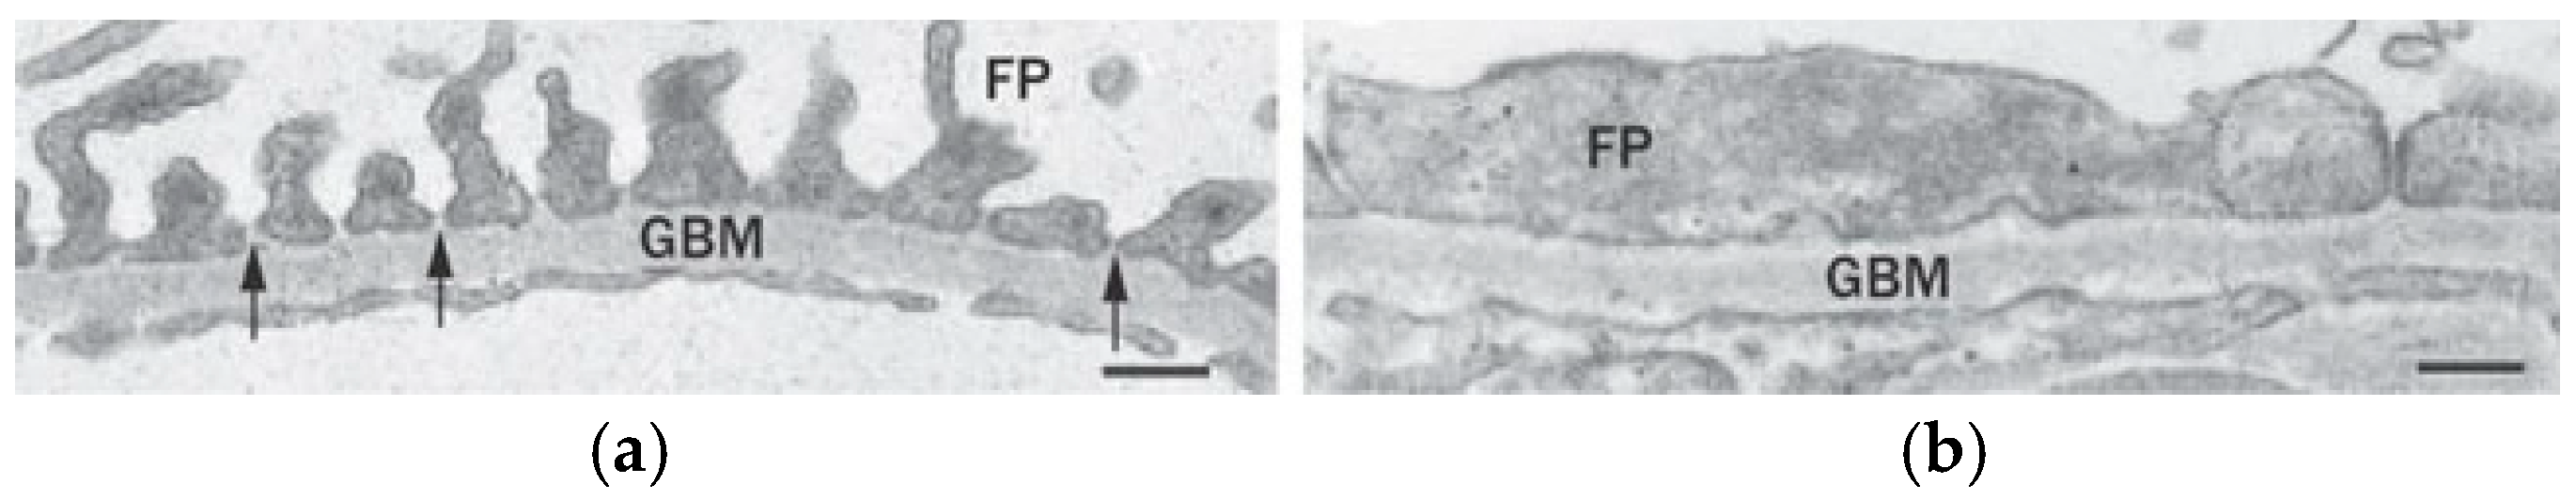

- Lahdenkari, A.-T.; Lounatmaa, K.; Patrakka, J.; Holmberg, C.; Wartiovaara, J.; Kestilä, M.; Koskimies, O.; Jalanko, H. Podocytes are firmly attached to glomerular basement membrane in kidneys with heavy proteinuria. J. Am. Soc. Nephrol. 2004, 15, 2611–2618. [Google Scholar] [CrossRef]